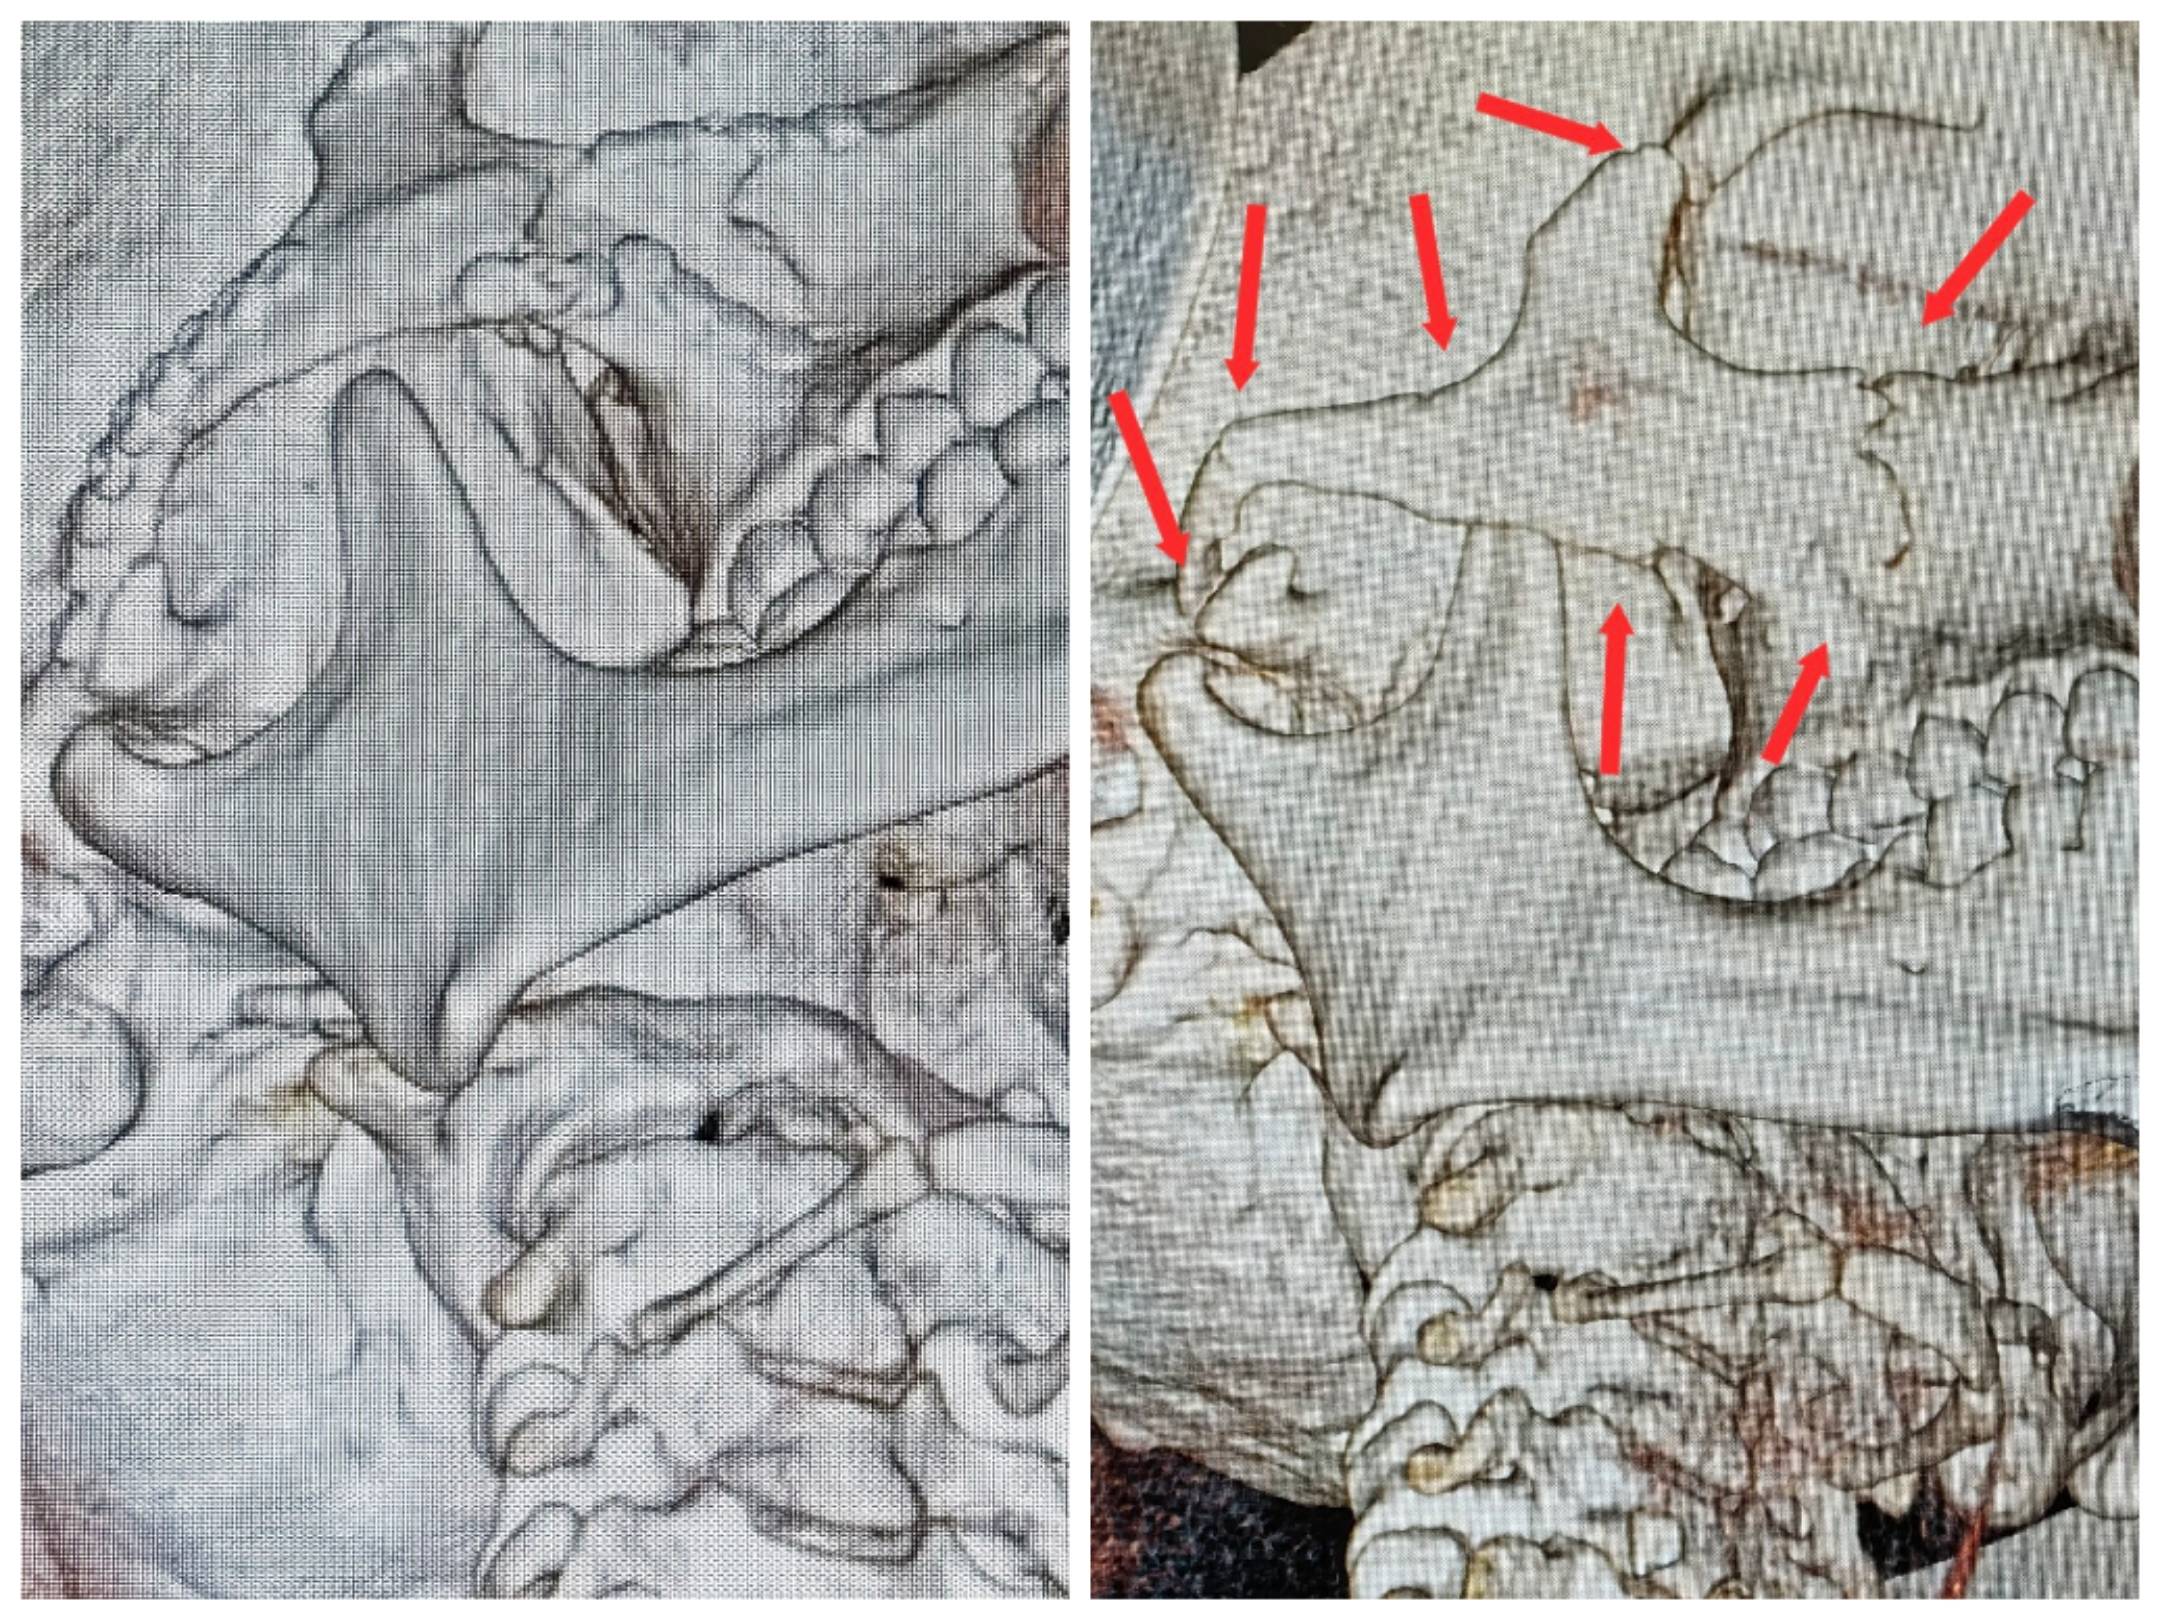

患者脸部七处粉碎性骨折分布位置

患者术前术后伤口对比图

“这类事故面临的不仅是外貌的恢复问题,更重要的是恢复口腔、咀嚼等功能,避免长期生活质量受损。”张琪介绍。在制订了详细的手术方案后,专家团队选择了隐蔽的切口,尽量避免面部留下显眼的疤痕,同时使用微型钛板,将碎裂的骨片一一复位并固定。任何角度的偏差,都会影响术后的外观和功能。张琪带领团队反复比对CT影像,通过术中导航精准定位,最终在显微视野下完成了骨折重建。

“颧弓复位后,我们又重新调整了咬合关系和肌肉牵拉角度,确保她今后张口、咀嚼不会受限。”张琪说。术后影像显示,王女士面部骨架恢复平整,面部线条自然流畅,功能与美观均达到了理想效果。